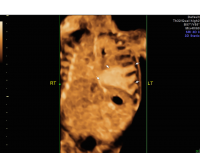

Bronchopulmonary sequestration 3D glass body doppler